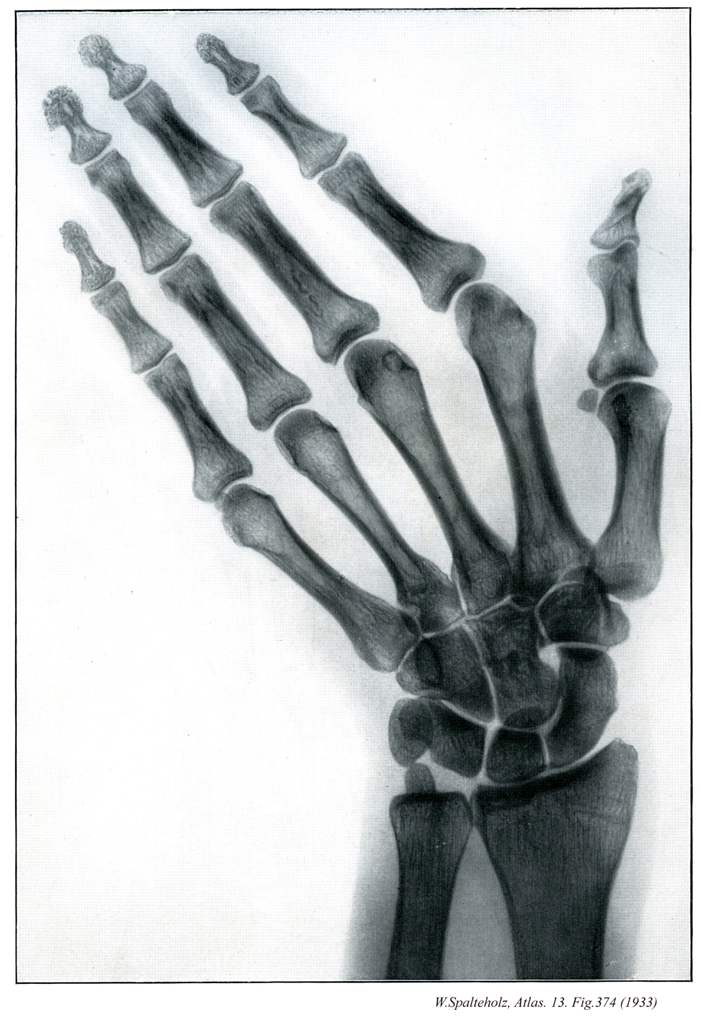

374

【Hand

手;テ

Manus】

→(手は上肢のうち橈骨手根関節より遠位の部分。手根と中手に区別され、手根と中手の前面を手掌、後面を手背という。皮膚節において第六頚神経、第七頚神経、第八頚神経のレベル。)